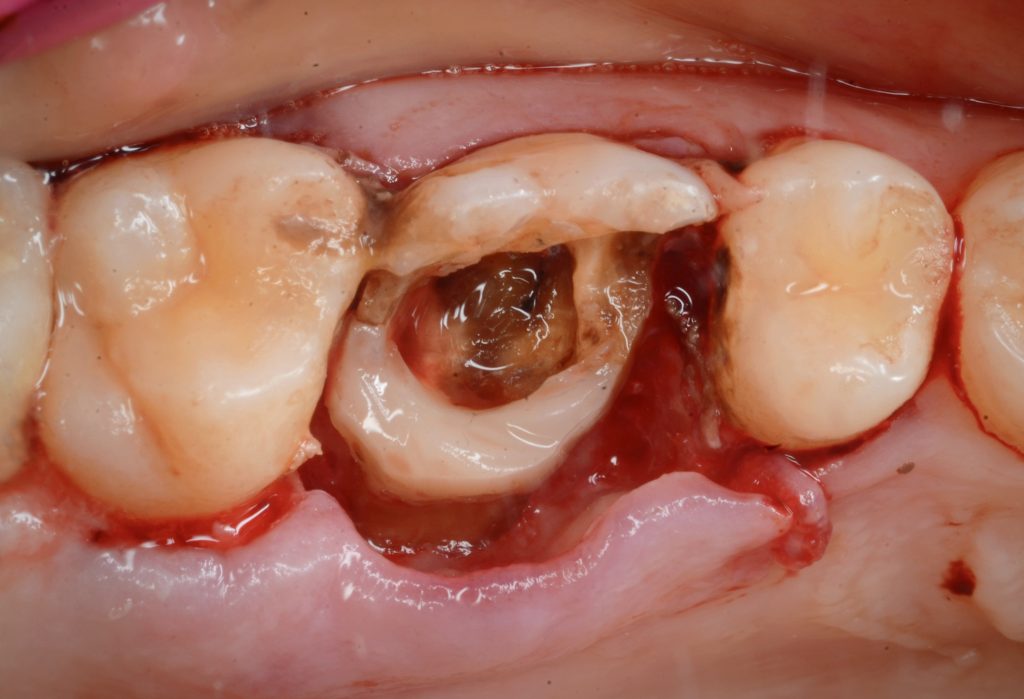

بعد إزالة الحشوة والبدء لبدء الجوتا بيرشا في الزيارة الأولى

في الزيارة الثانية لاحظنا كسر بصري في جدار الحنك (المريض في ذلك الوقت كان يعاني من الإجهاد ونير الأسنان أثناء النوم)

After first visit horizontal fracture occurred

Remove piece of fracture